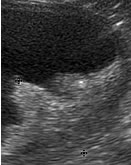

EYES

• Ultrasound is very useful in imaging retrobulbar masses and

assessing intraocular masses, retinal detachment and congenital

eye abnormalities.

Ocular tumour in the anterior chamber of the eye